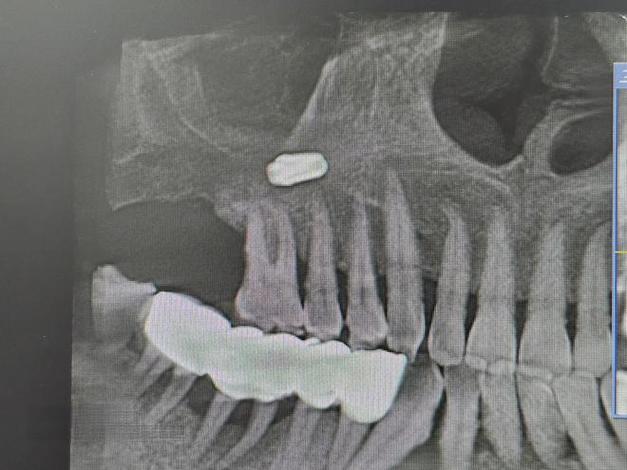

- 术前评估: 术前必须拍摄CBCT,精确测量上颌窦底骨壁厚度、形态,评估粘膜状况,对于骨壁极薄(<1mm)的患者,尤其要警惕。